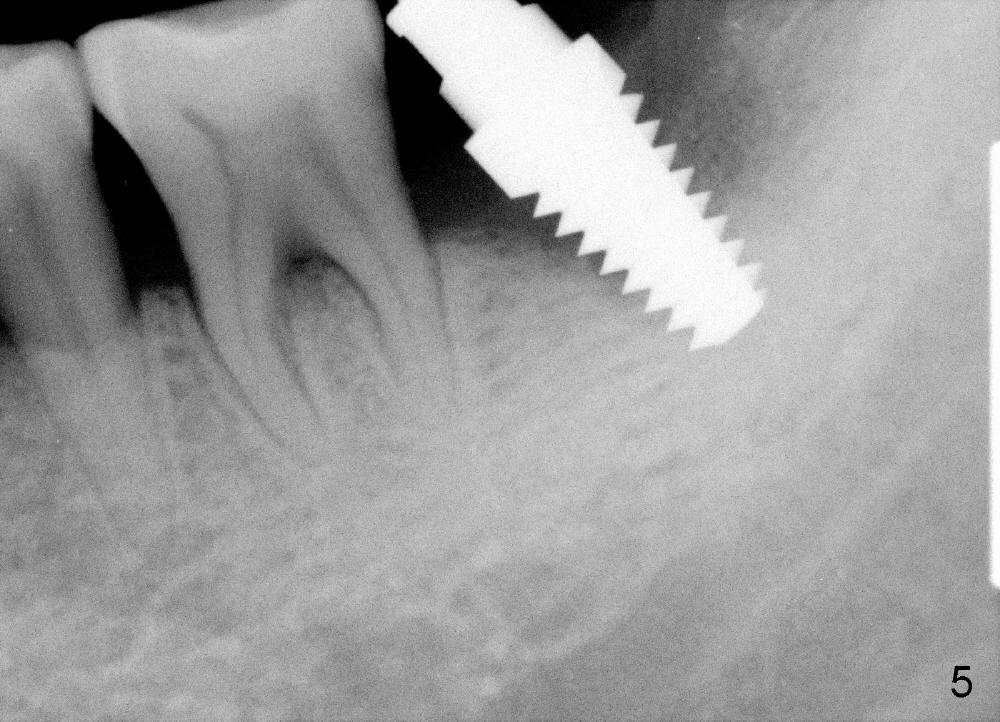

How about flatten the septum (Fig.4 white lines; from inset A (post extraction) to B)? When the septum is level with the mesial and distal sockets, a drill easily penetrates the middle of the socket (Fig.3 inset C). With strict control of depth, the osteotomy increases until a 6x14 mm tap gets initial binding to the socket (Fig.5: depth 11 mm). After increase in the depth by 1-2 mm, PA is taken with a 7x14 mm tap (Fig.6). There is a gap that the tap or the corresponding implant can engage further (between arrowheads). After increase in the diameter in the bottom of the osteotomy, a 7x11 mm implant is placed with insertion torque between 45 and 50 Ncm; the threads of the implant have tight contact with the bone (Fig.7). With the large diameter implant, the socket opening is closed without too much tension (Fig.8). The wound is protected with perio dressing. Postop there is no paresthesia. Pain is controlled by Hydrocodon/Acetaminophen. A long acting local anesthetic (Marcaine) should have been used immediately postop. Next morning, the patient is pain free. A short implant should be used in a critical area such as the lower 2nd molar where the inferior alveolar nerve is nearby. However, the implant is found unstable 1 month postop.